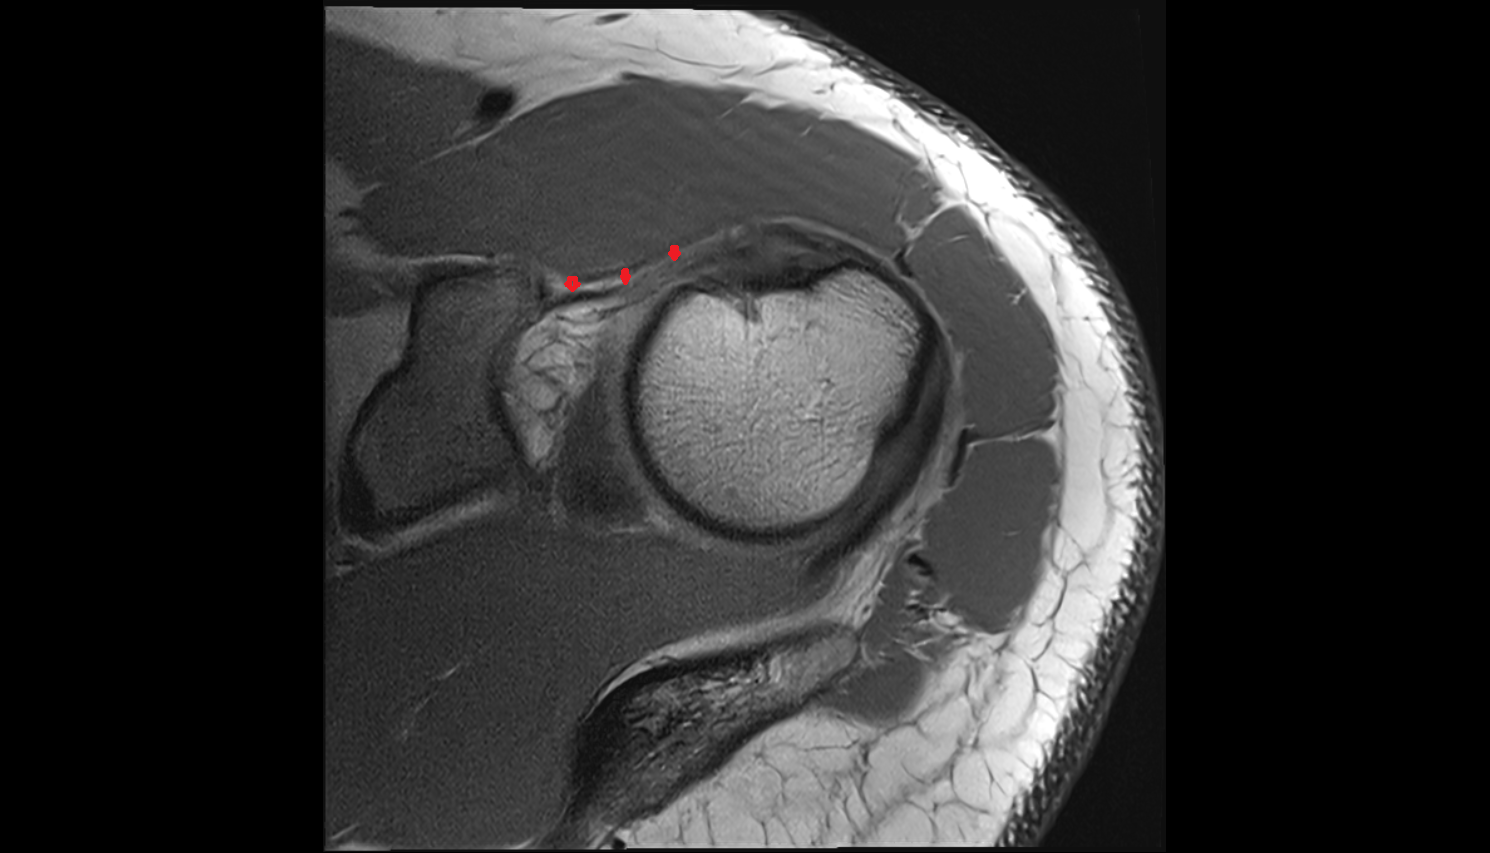

- Temporomandibular joint

- Articular disc of temporomandibular joint

- Articular eminence

- Mandibular condyle

- Intermediate zone of articular disc

- Superior retrodiscal layer